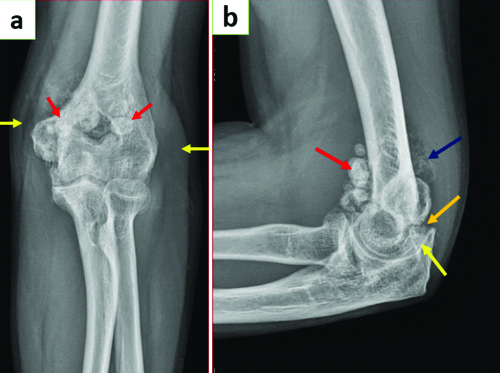

Static radiographs of the left elbow joint [Table/Fig-1a] reveal multiple well-defined round calcified extra-articular loose bodies around the elbow joint, accompanied by mild soft tissue swelling. The lateral view X-ray of the elbow joint [Table/Fig-1b] shows multiple extra-articular (both calcified and non calcified) loose bodies of varying sizes at the anterior and posterior aspects of the elbow joint. In addition to the extra-articular loose bodies, intra-articular loose bodies were also observed, resulting in the widening of the ulnohumeral joint space.

a) X-ray of left elbow joint in extension AP view showing multiple well-defined round calcified extra-articular loose bodies around the elbow joint (red arrows). Mild soft-tissue swelling around the joint is also noted (yellow arrows); b) X-ray of left elbow joint in flexion lateral view showing multiple extra-articular calcified (red arrow), extra-articular non calcified (blue arrow) loose bodies of varying sizes seen at the anterior and posterior aspects of the elbow joint. Intra-articular loose bodies (orange arrow) also seen resulting in widening of ulno-humeral joint space (yellow arrow).